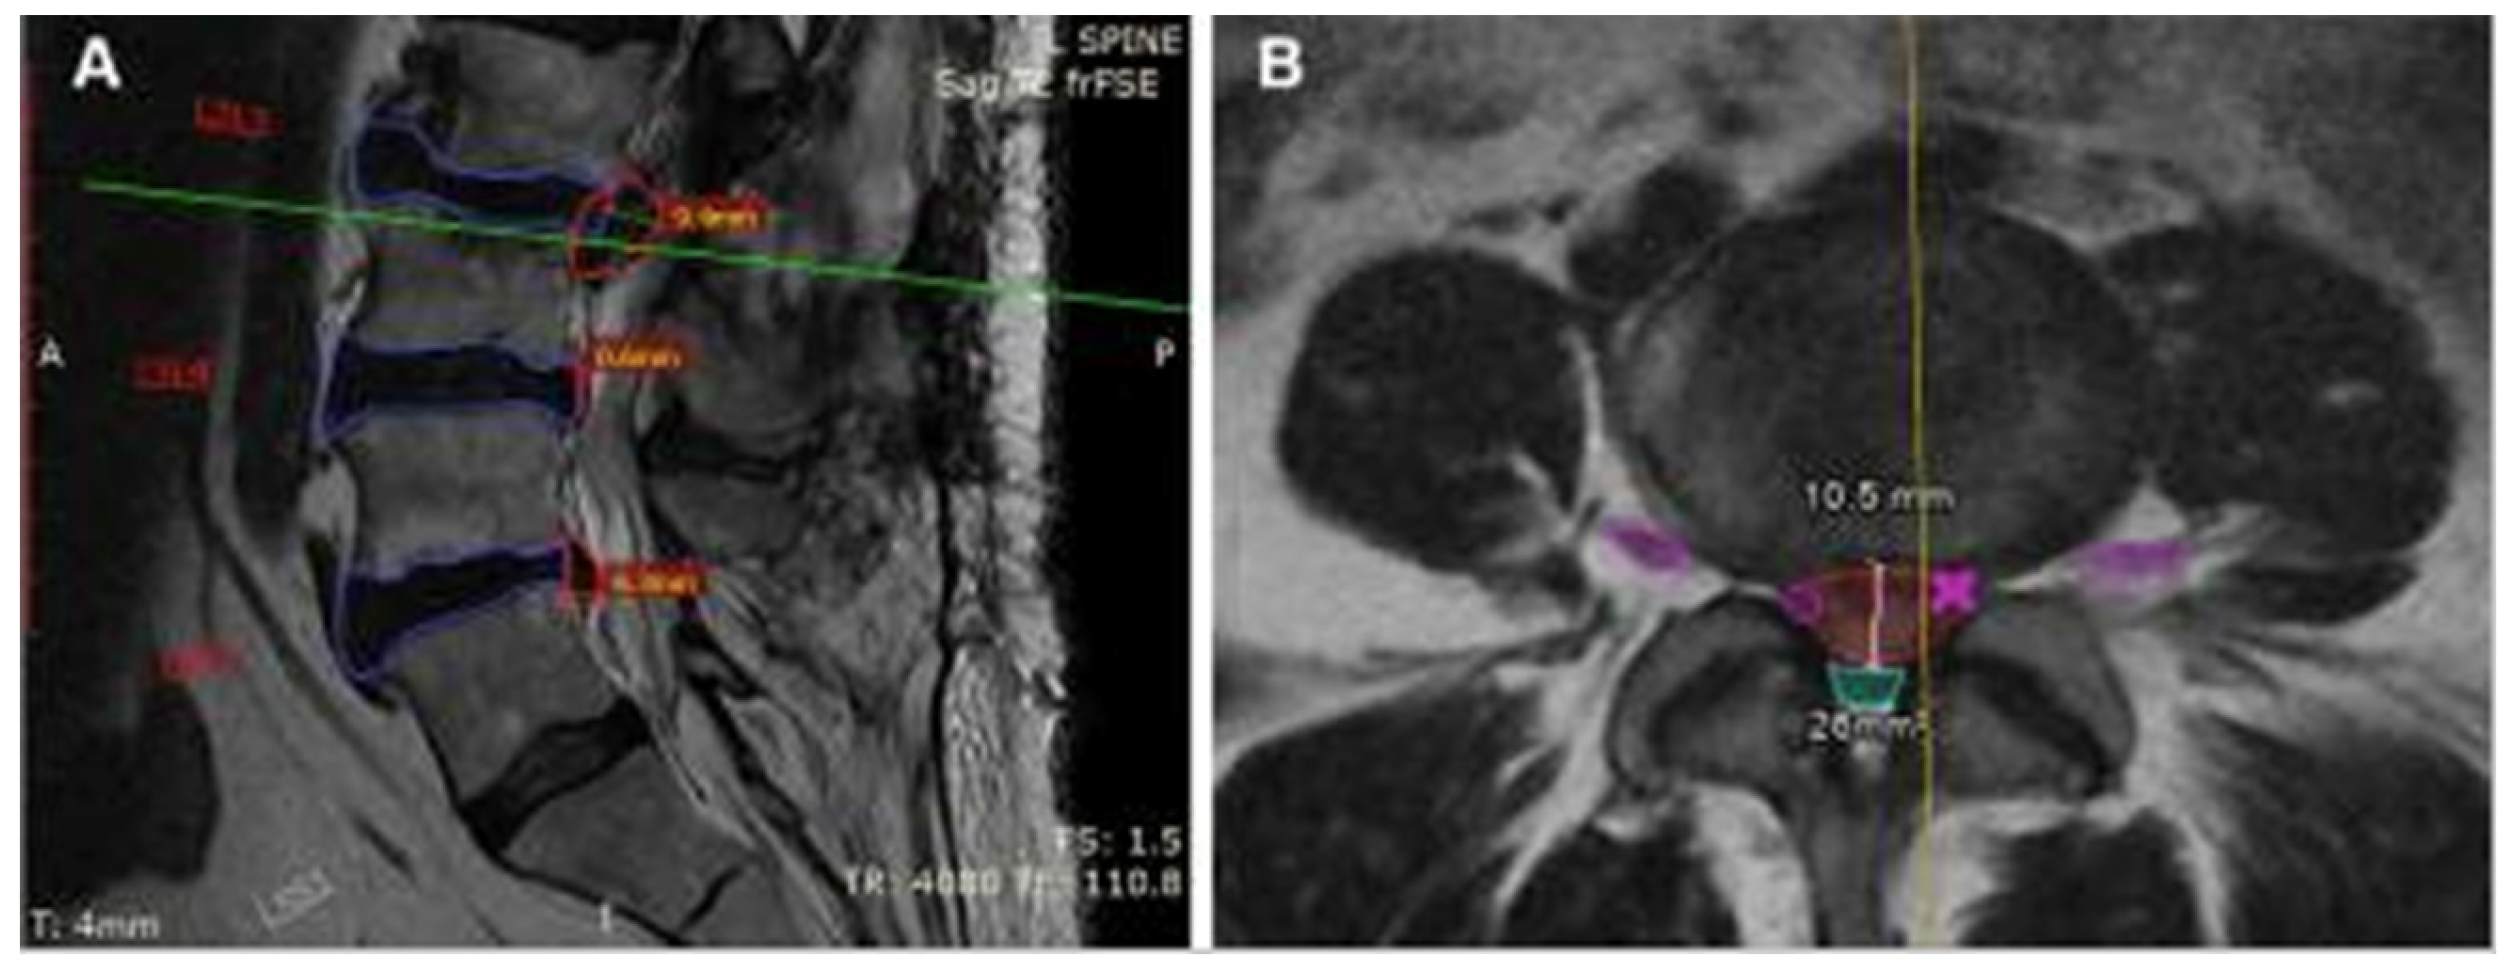

Figure 2. MRI of the lumbar spine in a 68-year-old woman using sagittal (A) and axial (B) T2-weighted fast spin-echo sequences. CoLumbo software (Smart Soft Healthcare) automatically segments key spinal structures—vertebral discs (blue), herniated discs (red), dural sac (cyan), and foraminal nerve roots (pink)—and quantifies herniation size and dural sac area. Green and yellow lines indicate the levels corresponding to the axial and sagittal views, respectively. Imaging parameters include repetition time (TR) and echo time (TE) in milliseconds; scale bar = 5 mm [3].